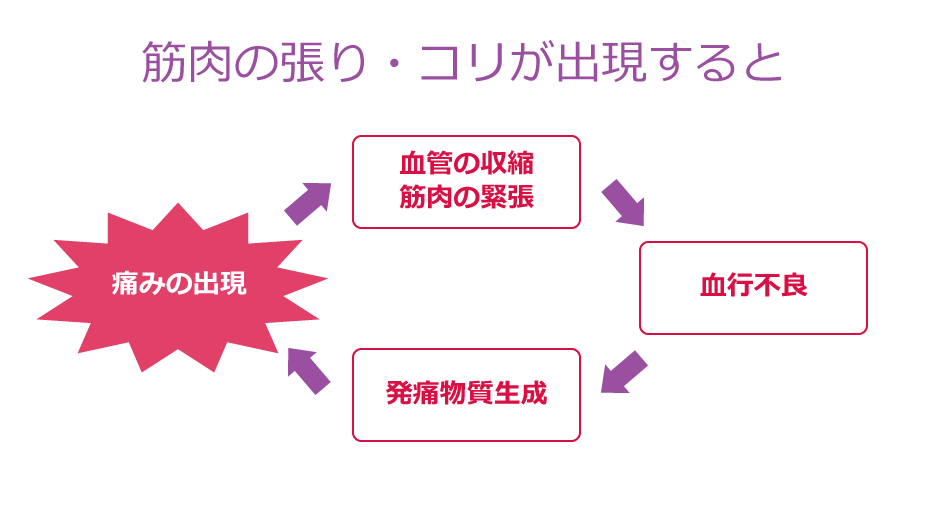

慢性症状に対しては、ちゃんとしたマッサージを行い、筋肉の緊張を緩和し血行をよくした上でハイボルテージ治療を行うことがより効果的と考えます!